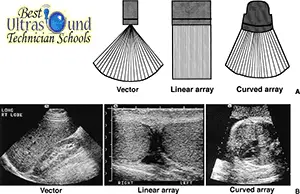

Detecting bladder cancer with ultrasound

An ultrasound (which may also be referred to as a sonogram) uses high frequency sound waves to produce images of internal organs. Echoes, which are created as sound waves bounce off organs and tissues, produce computer images that provide information on the structure and movement of organs and the blood flow through vessels.

An ultrasound of the urinary tract can help assess the size of a bladder tumor and whether a bladder cancer has spread. Ultrasound is able to differentiate between fluid-filled cysts and solid tumors, however, it cannot determine if a tumor is cancerous. Ultrasound can also be used to guide a biopsy needle to sample a suspected cancer.

Ultrasound scans use high frequency sound waves to create a picture of a part of the body. You have an ultrasound scan of your tummy (abdomen) to look at your urinary system (the bladder, kidneys, ureter and urethra).

How does an ultrasound scanner work?

The ultrasound scanner has a microphone that gives off sound waves. The sound waves bounce off the organs inside your body, and the microphone picks them up. The microphone links to a computer that turns the sound waves into a picture on the screen. Ultrasound scans are completely painless. You usually have the scan in the hospital x-ray department …